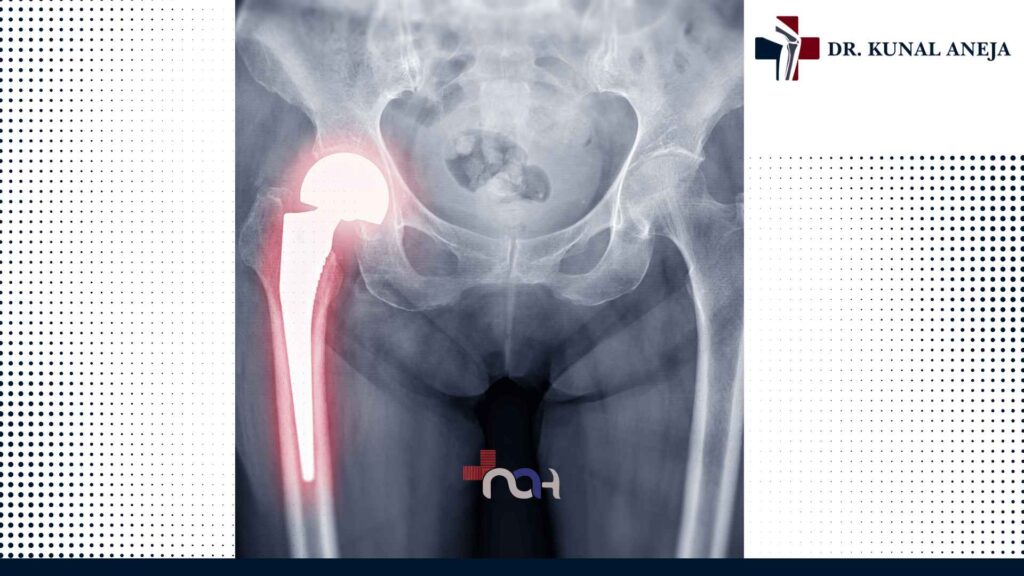

Total Hip Replacement in Delhi – Step-by-Step Treatment

Looking for Total Hip Replacement in Delhi? Dr. Kunal Aneja provides a step-by-step approach for expert care, precise surgery, and improved mobility.